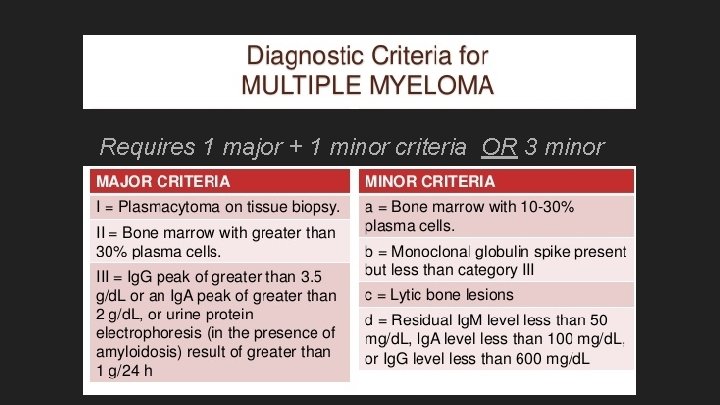

Requires 1 major + 1 minor criteria OR 3 minor

Requires 1 major + 1 minor criteria OR 3 minor criteria